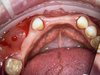

· Проведение хирургических вмешательств с фокусом на полную реабилитацию (All-on-4/6) с немедленной нагрузкой.

· Хирургическое лечение полного спектра случаев: от единичных имплантаций до комплексных реабилитаций.

· Проведение пластики мягких тканей для обеспечения долгосрочной стабильности и эстетики десневого контура.

· Комплексная имплантация: All-on-4, All-on-6 (FP-1), одномоментная и отсроченная имплантация.

· Хирургия мягких тканей: пластика рецессий (tunneling technique), вестибулопластика, пластика уздечек, закрытие соустья.